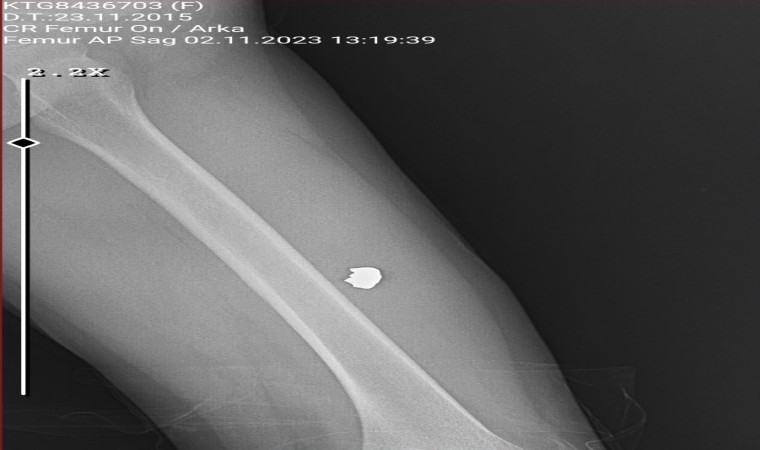

Bacağındaki kurşun çıkartıldı

Kavgada hiçbir suçu yokken sol bacağına isabet eden kurşunla yaralanan 8 yaşındaki Sinem Uça ise Antalya Eğitim Araştırma Hastanesi’nde tedavi altına alındı. Burada operasyon geçiren Sinem’in baldır kısmından giren kurşun çıkartıldı. Yaklaşık 6 saatlik tedavinin ardından küçük kız taburcu olup evine gönderildi.